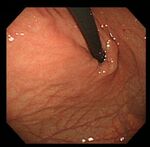

要確認、あなたは「ピロリ菌」に感染していないか?